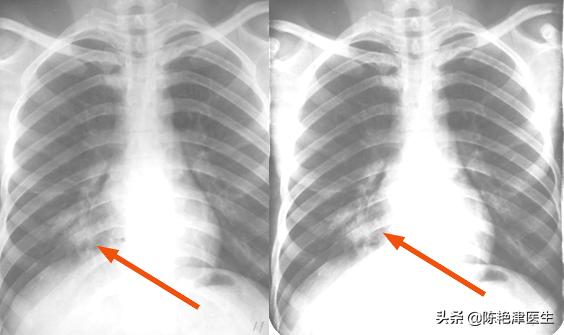

胸部增强CT显示: 右肺下叶外后基底段见结节样高密度阴影 ,内密度欠均匀,淋巴结肿大,边界是清晰的,发现支气管炎,肺气肿,双肺炎性病变。

活检显示: 免疫组化90%,见小细胞癌。

确诊:小细胞肺癌 。

医生解释道: “您的这个外在表现并不明显,但是从胸片结果上和活检结果上看,确实是肺癌。”张先生:“那是什么原因呢? 我平时都不抽烟的人 ,怎么可能是肺癌呢?”